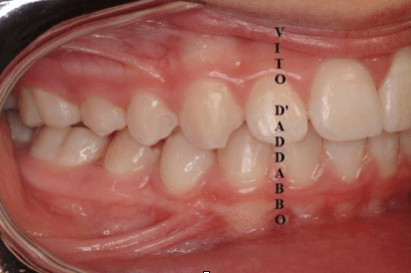

In una bocca che chiude correttamente i denti dell’arcata superiore sono collocati più esternamente rispetto ai corrispondenti dell’arcata inferiore. Nel morso inverso accade il contrario: in quello laterale sono i denti inferiori laterali a chiudere esternamente.

Questa malocclusione è il più delle volte dovuta a un mascellare piccolo, come nel caso riportato, dove manca anche lo spazio per l’incisivo laterale permanente di sinistra. I morsi incrociati vanno corretti precocemente perché possono provocare gravi asimmetrie del viso.